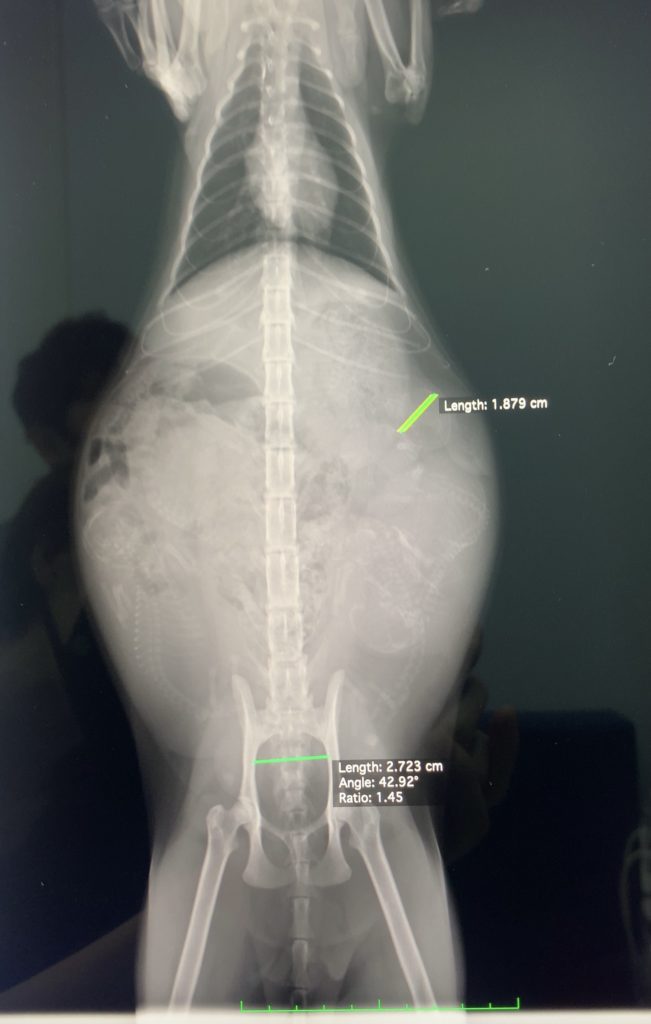

先月より200グラム近く増え、エコーとレントゲン写真で5匹の赤ちゃんが確認されました。しかも今週か来週中にも産まれるという!!おめでたい!

まじまじとレントゲン写真をみると、お腹の中いっぱいに赤ちゃんがぎゅうぎゅうに入ってて、ごちゃごちゃしているなぁ笑